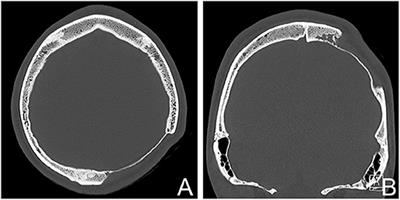

Disappearing Calvarium In Gorham Disease Mr Imaging Characteristics With Pathologic Correlation American Journal Of Neuroradiology

Frontiers A Large Skull Defect Due To Gorham Stout Disease Case Report And Literature Review On Pathogenesis Diagnosis And Treatment Endocrinology

Figure 1 From A Case Of Vanishing Skull Gorham S Disease Semantic Scholar

Complex Single Step Skull Reconstruction In Gorham S Disease A Technical Report And Review Of The Literature Bmc Surgery Full Text

Gorham S Disease Ct Scans Stock Image C015 5085 Science Photo Library